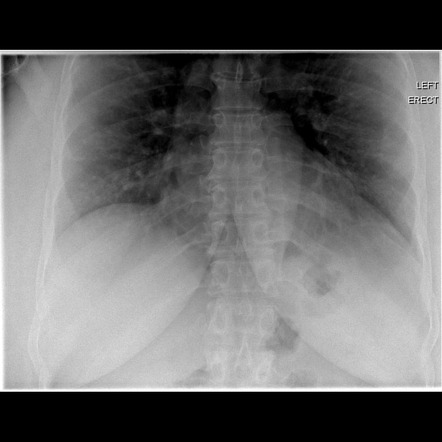

Pneumoperitoneum and subphrenic abscess are two important differential diagnosis of this radiographic sign which can be excluded out when normal plicae circulares or haustral markings of the colon is seen under the right diaphragm. If youre experiencing mild discomfort in your diaphragm take a few minutes to concentrate on deep breathing. Treatment depends on the type of hiatal hernia you have and on your symptoms.

Place one hand on your abdomen and breathe deeply. Reduced number of alveoli air sacs required for normal breathing. In severe cases when there is no simple treatment that can relieve dyspnea your doctor may prescribe morphine. Congenital diaphragmatic hernia CDH. There is usually a long history of heavy smoking. Shortness of breath may be accompanied by wheezing. Diaphragmatic dysfunction caused by transverse myelitis or leukemic infiltration of the cervical spinal cord in a patient with leukemia and shortness of breath. To treat phrenic nerve irritation This condition can be managed with a breathing pacemaker which takes over the responsibility of sending messages to the diaphragm. The cause for shortness of breath was thought primarily due to stable angina on tread mill test positive finding but Chilaiditis syndrome should also be considered as a cause for the shortness of breath.

The rise in intraabdominal pressure further increases intrathoracic and lung volume by pushing the lower rib cage outward. In severe cases when there is no simple treatment that can relieve dyspnea your doctor may prescribe morphine. Diaphragmatic dysfunction caused by transverse myelitis or leukemic infiltration of the cervical spinal cord in a patient with leukemia and shortness of breath. Diaphragmatic plication a surgical procedure that pulls the diaphragm down by introducing a repeated series of continuous sutures across the diaphragm and pulling the muscle taut. A bedside fan or open window with a breeze are also simple but very effective treatments to lessen dyspnea. Depending on the severity of injury to the diaphragm some doctors recommend non-surgical options to treat the breathing issues associated with diaphragm weakness and paralysis. P E Pulmonary embolism.